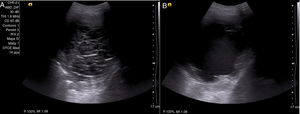

Con el diagnóstico de DPM secundario a neoplasia renal en estadio iv, y ante la persistencia de derrame pleural, se decide, tras explicarle las distintas alternativas terapéuticas al paciente, la colocación de un DT (IPC™ Pleural catheter, Rocket Medical©, Watford, Reino Unido), instruyendo tanto al paciente como a familiares para su drenaje en domicilio. A los 30 días, aproximadamente, de la colocación del DT, acude a la consulta con disnea de pequeños esfuerzos (escala visual analógica [EVA]: 8/10, disnea según el modified Medical Research Council: III) y sin presentar débito eficaz a través del DT. En la radiografía de tórax, se observa un derrame pleural derecho ii/iv, sin cambios respecto a estudios previos con catéter bien colocado en el hemitórax derecho. Se realiza una ecografía torácica en la que se objetiva un derrame ii/iv, con múltiples septos y detritus en su interior (fig. 1 A). Se realiza una instilación de uroquinasa intrapleural de 100.000 UI, se deja actuar durante 2h y se repite según protocolo una ecografía torácica; en ella se demuestra una lisis total de los septos, persistiendo el derrame pleural con detritus (fig. 1 B). Se procede al drenaje del mismo, obteniendo 750ml de líquido serohemático, sin complicaciones asociadas y con importante alivio sintomático.

Paciente de 61 años, con derrame pleural maligno secundario a neoplasia renal estadio iv, que acude por cese del drenaje a través de catéter tunelizado. Se realiza una ecografía torácica en la que se objetivan numerosos septos que impiden el drenaje del líquido pleural (A). Se procede a la instilación de una única dosis de uroquinasa 100.000 UI y se deja actuar durante 2h; posteriormente, se repite la ecografía torácica, en la que se observa un derrame pleural libre con detritus en su interior y una lisis de los septos (B). Se procede entonces a su drenaje con un débito de 750ml de líquido pleural serohemático y una mejoría sintomática posterior del paciente.